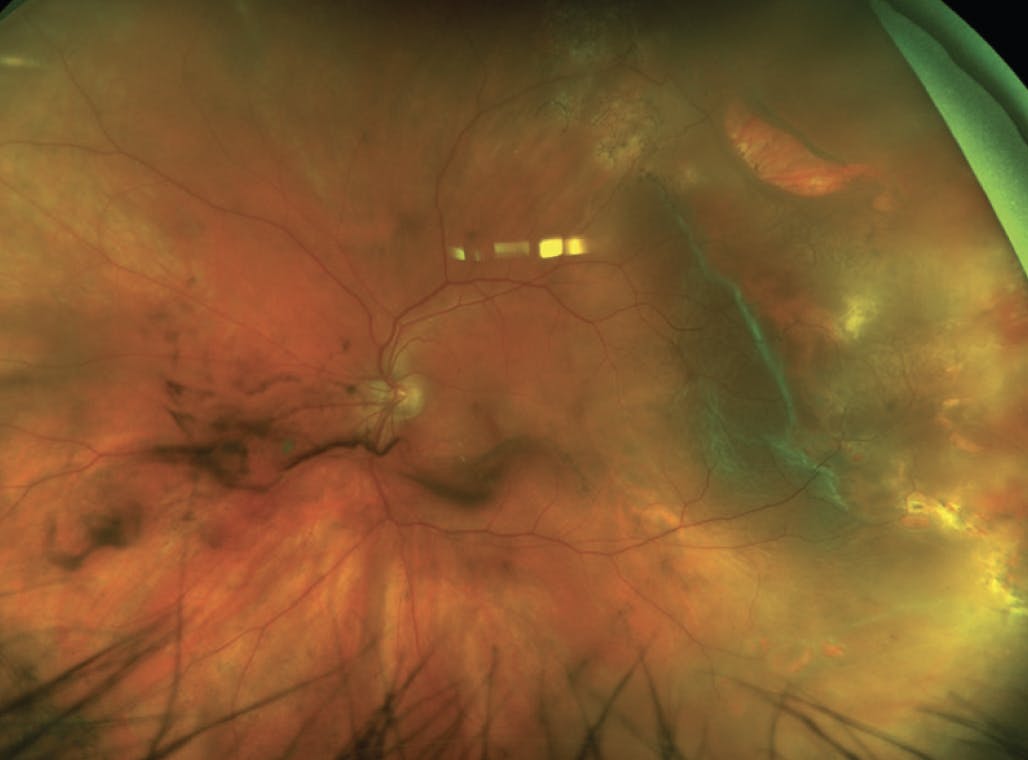

When encountering a primary RRD, several risk factors for PVR have been previously described, including vitreous hemorrhage, preoperative PVR, large or chronic detachments, large or multiple retinal breaks, choroidal detachment, intraocular inflammation, and extensive cryotherapy (Figure 1).2 However, limited studies exist that evaluate the role of these high-risk features on RRD repair outcomes and whether such risk factors truly influence single-surgery anatomic success (SSAS) in primary RRD.

Figure 1. In this patient who presented with a high-risk RRD, vitreous hemorrhage and multiple breaks are present. The larger break superotemporally has rolled edges, consistent with PVR grade B.